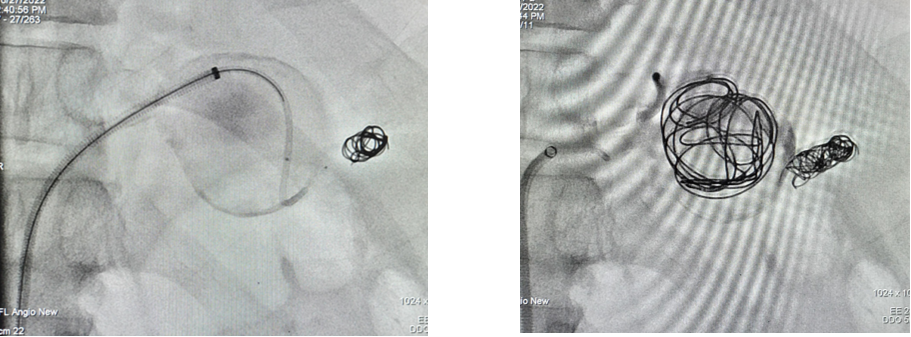

病例4 两端栓塞+瘤腔填塞

病例5 多发动脉瘤分支+主干栓塞

图为:分支栓塞

图为:主干栓塞最后造影